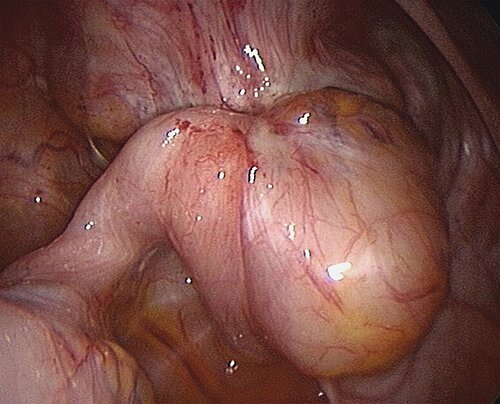

Ovarielle Endometriose

Insbesondere bei Patientinnen mit Kinderwunsch ist große Vorsicht bei der operativen Therapie der Endometriome geboten, da mit jedem operativen Eingriff eine Verringerung der ovariellen Reserve verbunden ist. Dies trifft insbesondere auf die Entfernung des Zystenbalges zu, da hierbei gleichzeitig gesundes Ovargewebe mitentfernt wird; Entscheidungskriterien sind in Tab. 2 aufgeführt. Deutlich schonender verlaufen die Punktion der Zyste mit anschließender Alkoholinstillation bzw. die Eröffnung der Zyste mit anschließender Plasmakoagulation des Zystenbalges. Eine präoperative Aufklärung der Patientinnen über die Möglichkeiten und Kosten des Medical (Social) Freezings ist hilfreich.